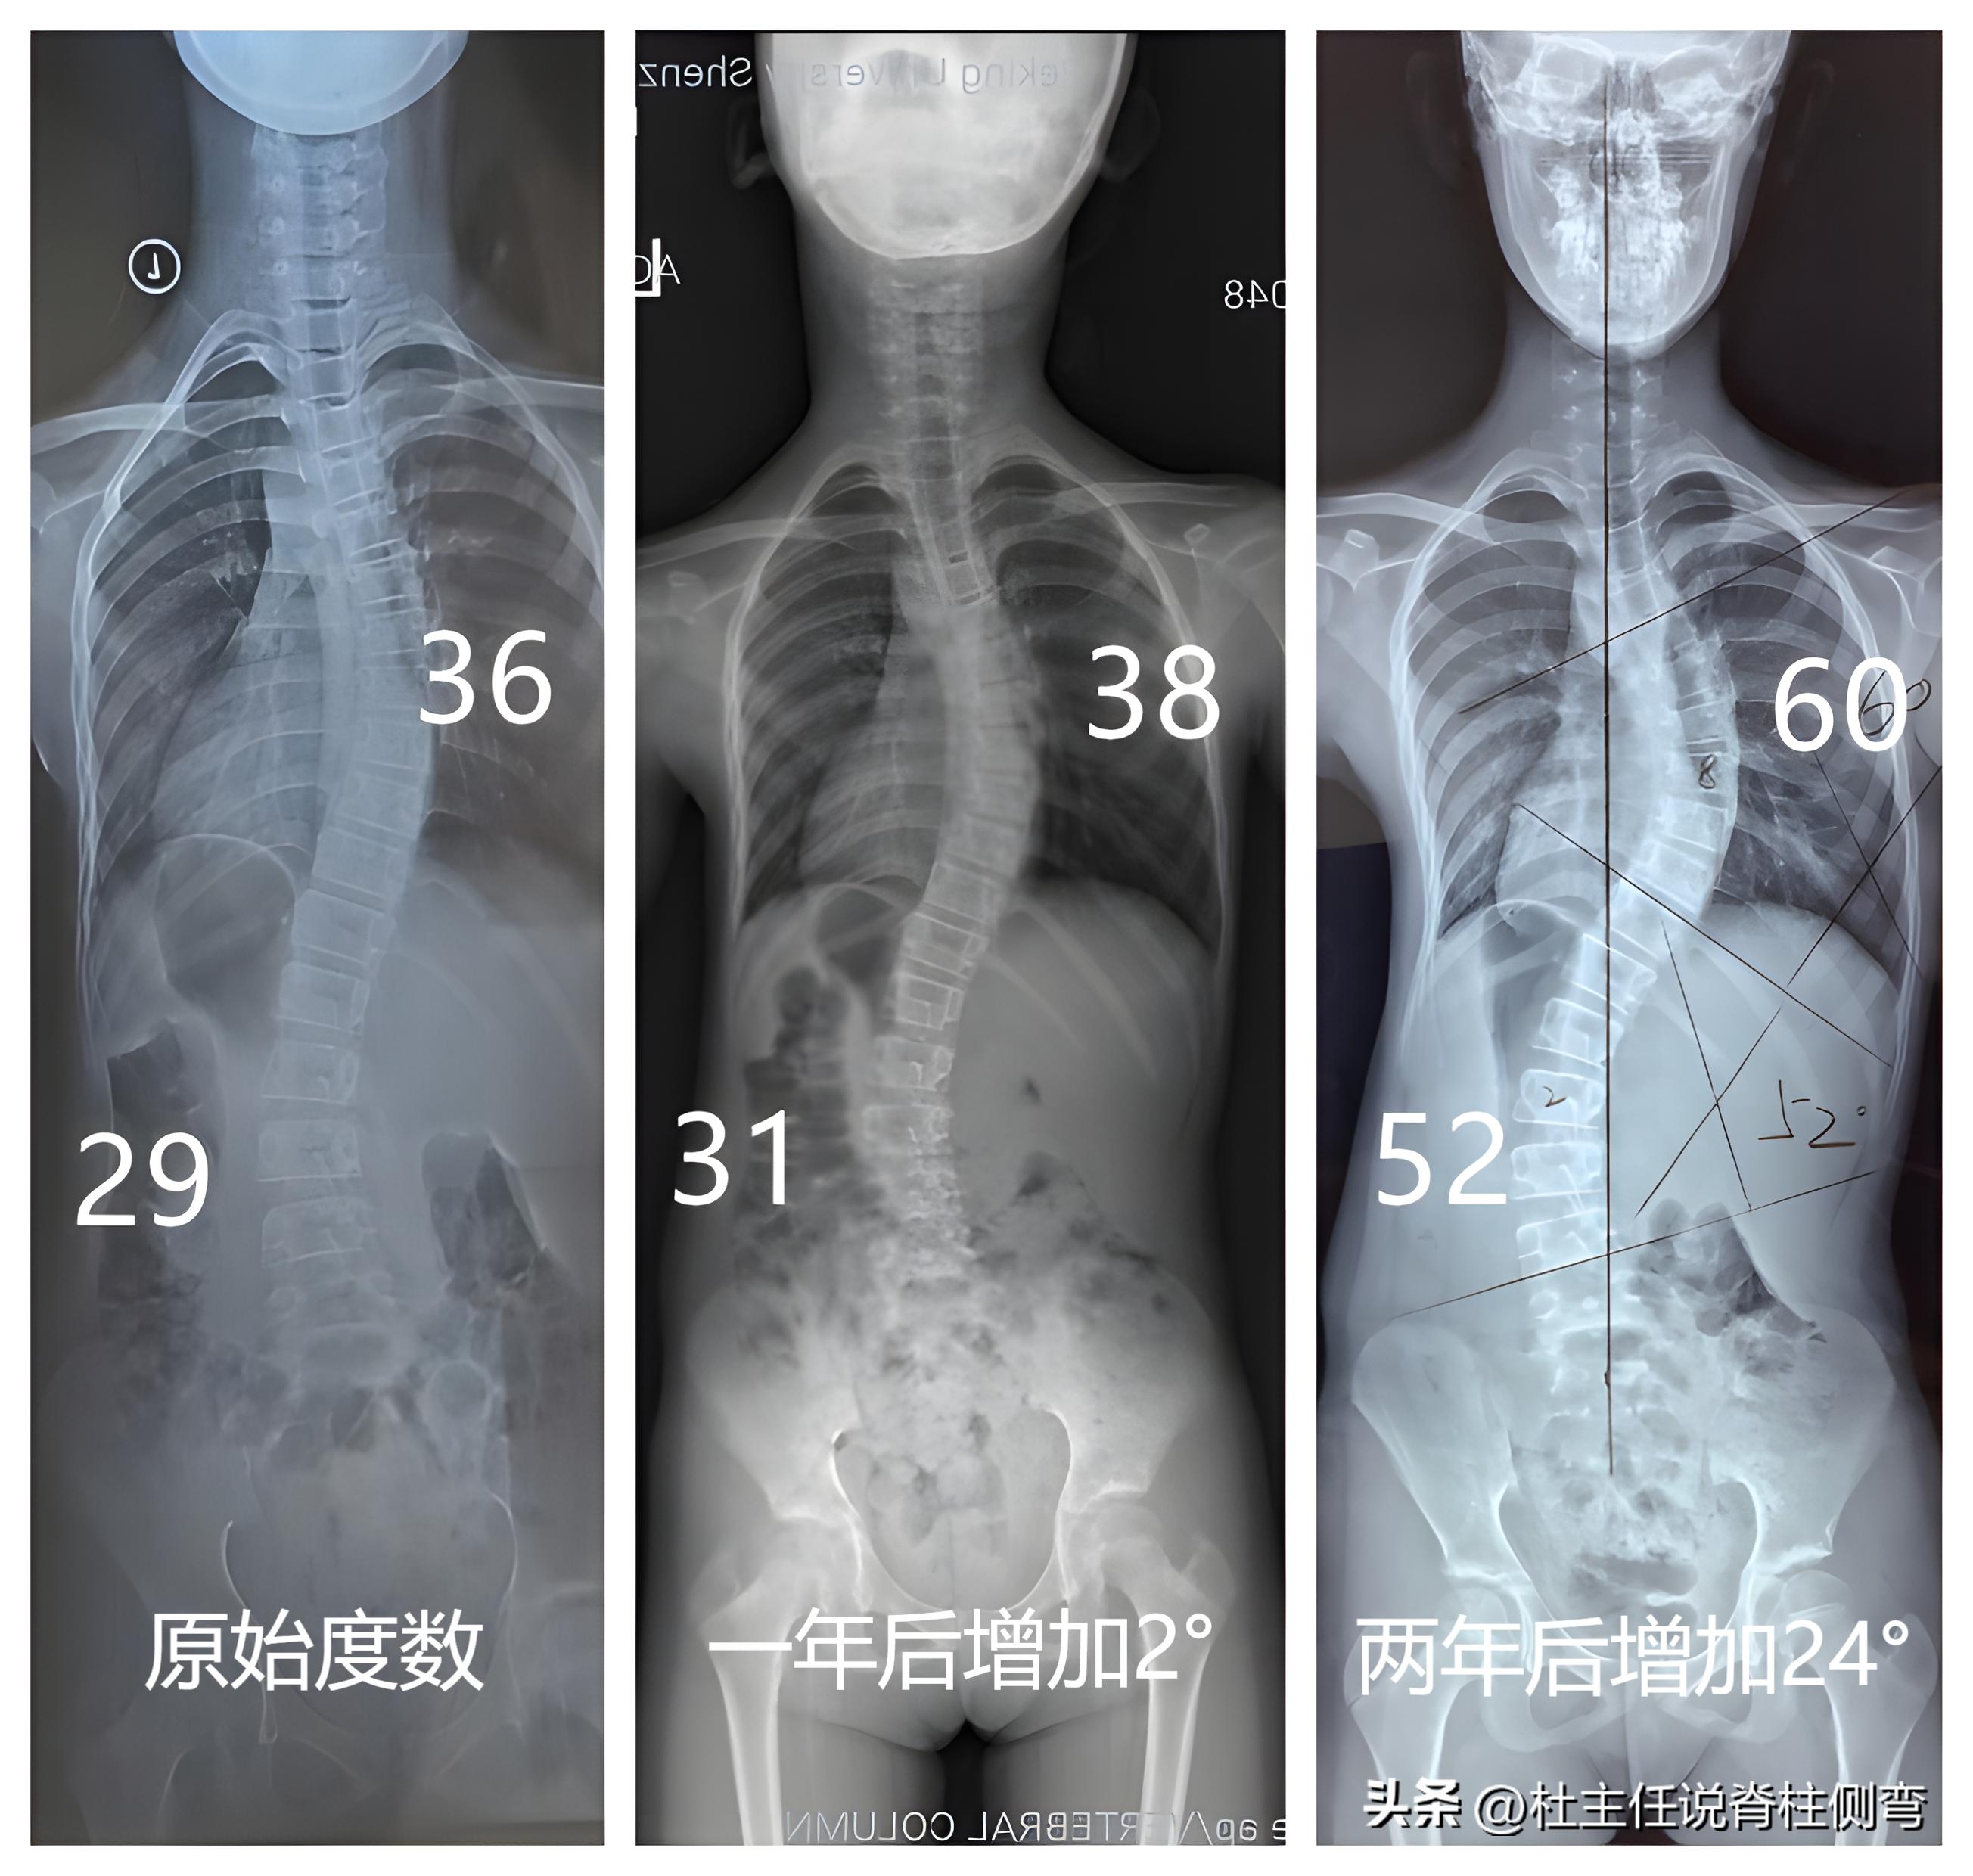

11岁女孩小前,2020年在学校体检时,被发现腰背部肌肉不对称,后来家长带她去医院拍片检查发现, 胸椎度数36°,腰椎度数29° 。当时家长并不清楚病情的严重性, 没有 太过在意,也没有让孩子接受相关的治疗。

一年后拍片复查,度数分别增加了2°。又过了一年后再次复查,结果让人大吃一惊,度数已经增长到了 60°和52° ,整整翻了接近一倍。